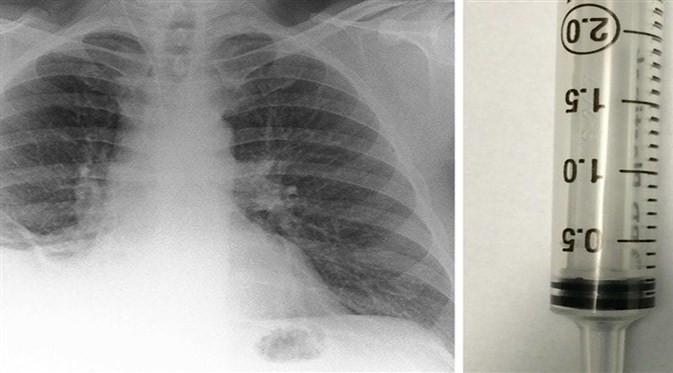

Setelah melakukan pemeriksaan lewat sinar X, dokter mendiagnosis Paul dengan tumor ganas, karena dari hasil pemeriksaan tampak sebuah benda menyerupai tumor di paru-paru sebelah kanan.

Diagnosis itu tak lama berubah, saat dokter kembali melakukan pengecekan menggunakan bronchoscopy, prosedur yang memungkinkan dokter melihat saluran pernapasan pasien menggunakan alat bronchoscope.

Dokter di Royal Preston Hospital, menemukan, ada miniatur traffic cone berukuran kecil bersarang di paru-paru Paul.

Akhirnya, dokter mengeluarkan mainan kerucut lalu lintas dengan forsep (alat menyerupai sendok) pada 2015, tepat 40 tahun miniatur traffic cone tertelan oleh Paul.